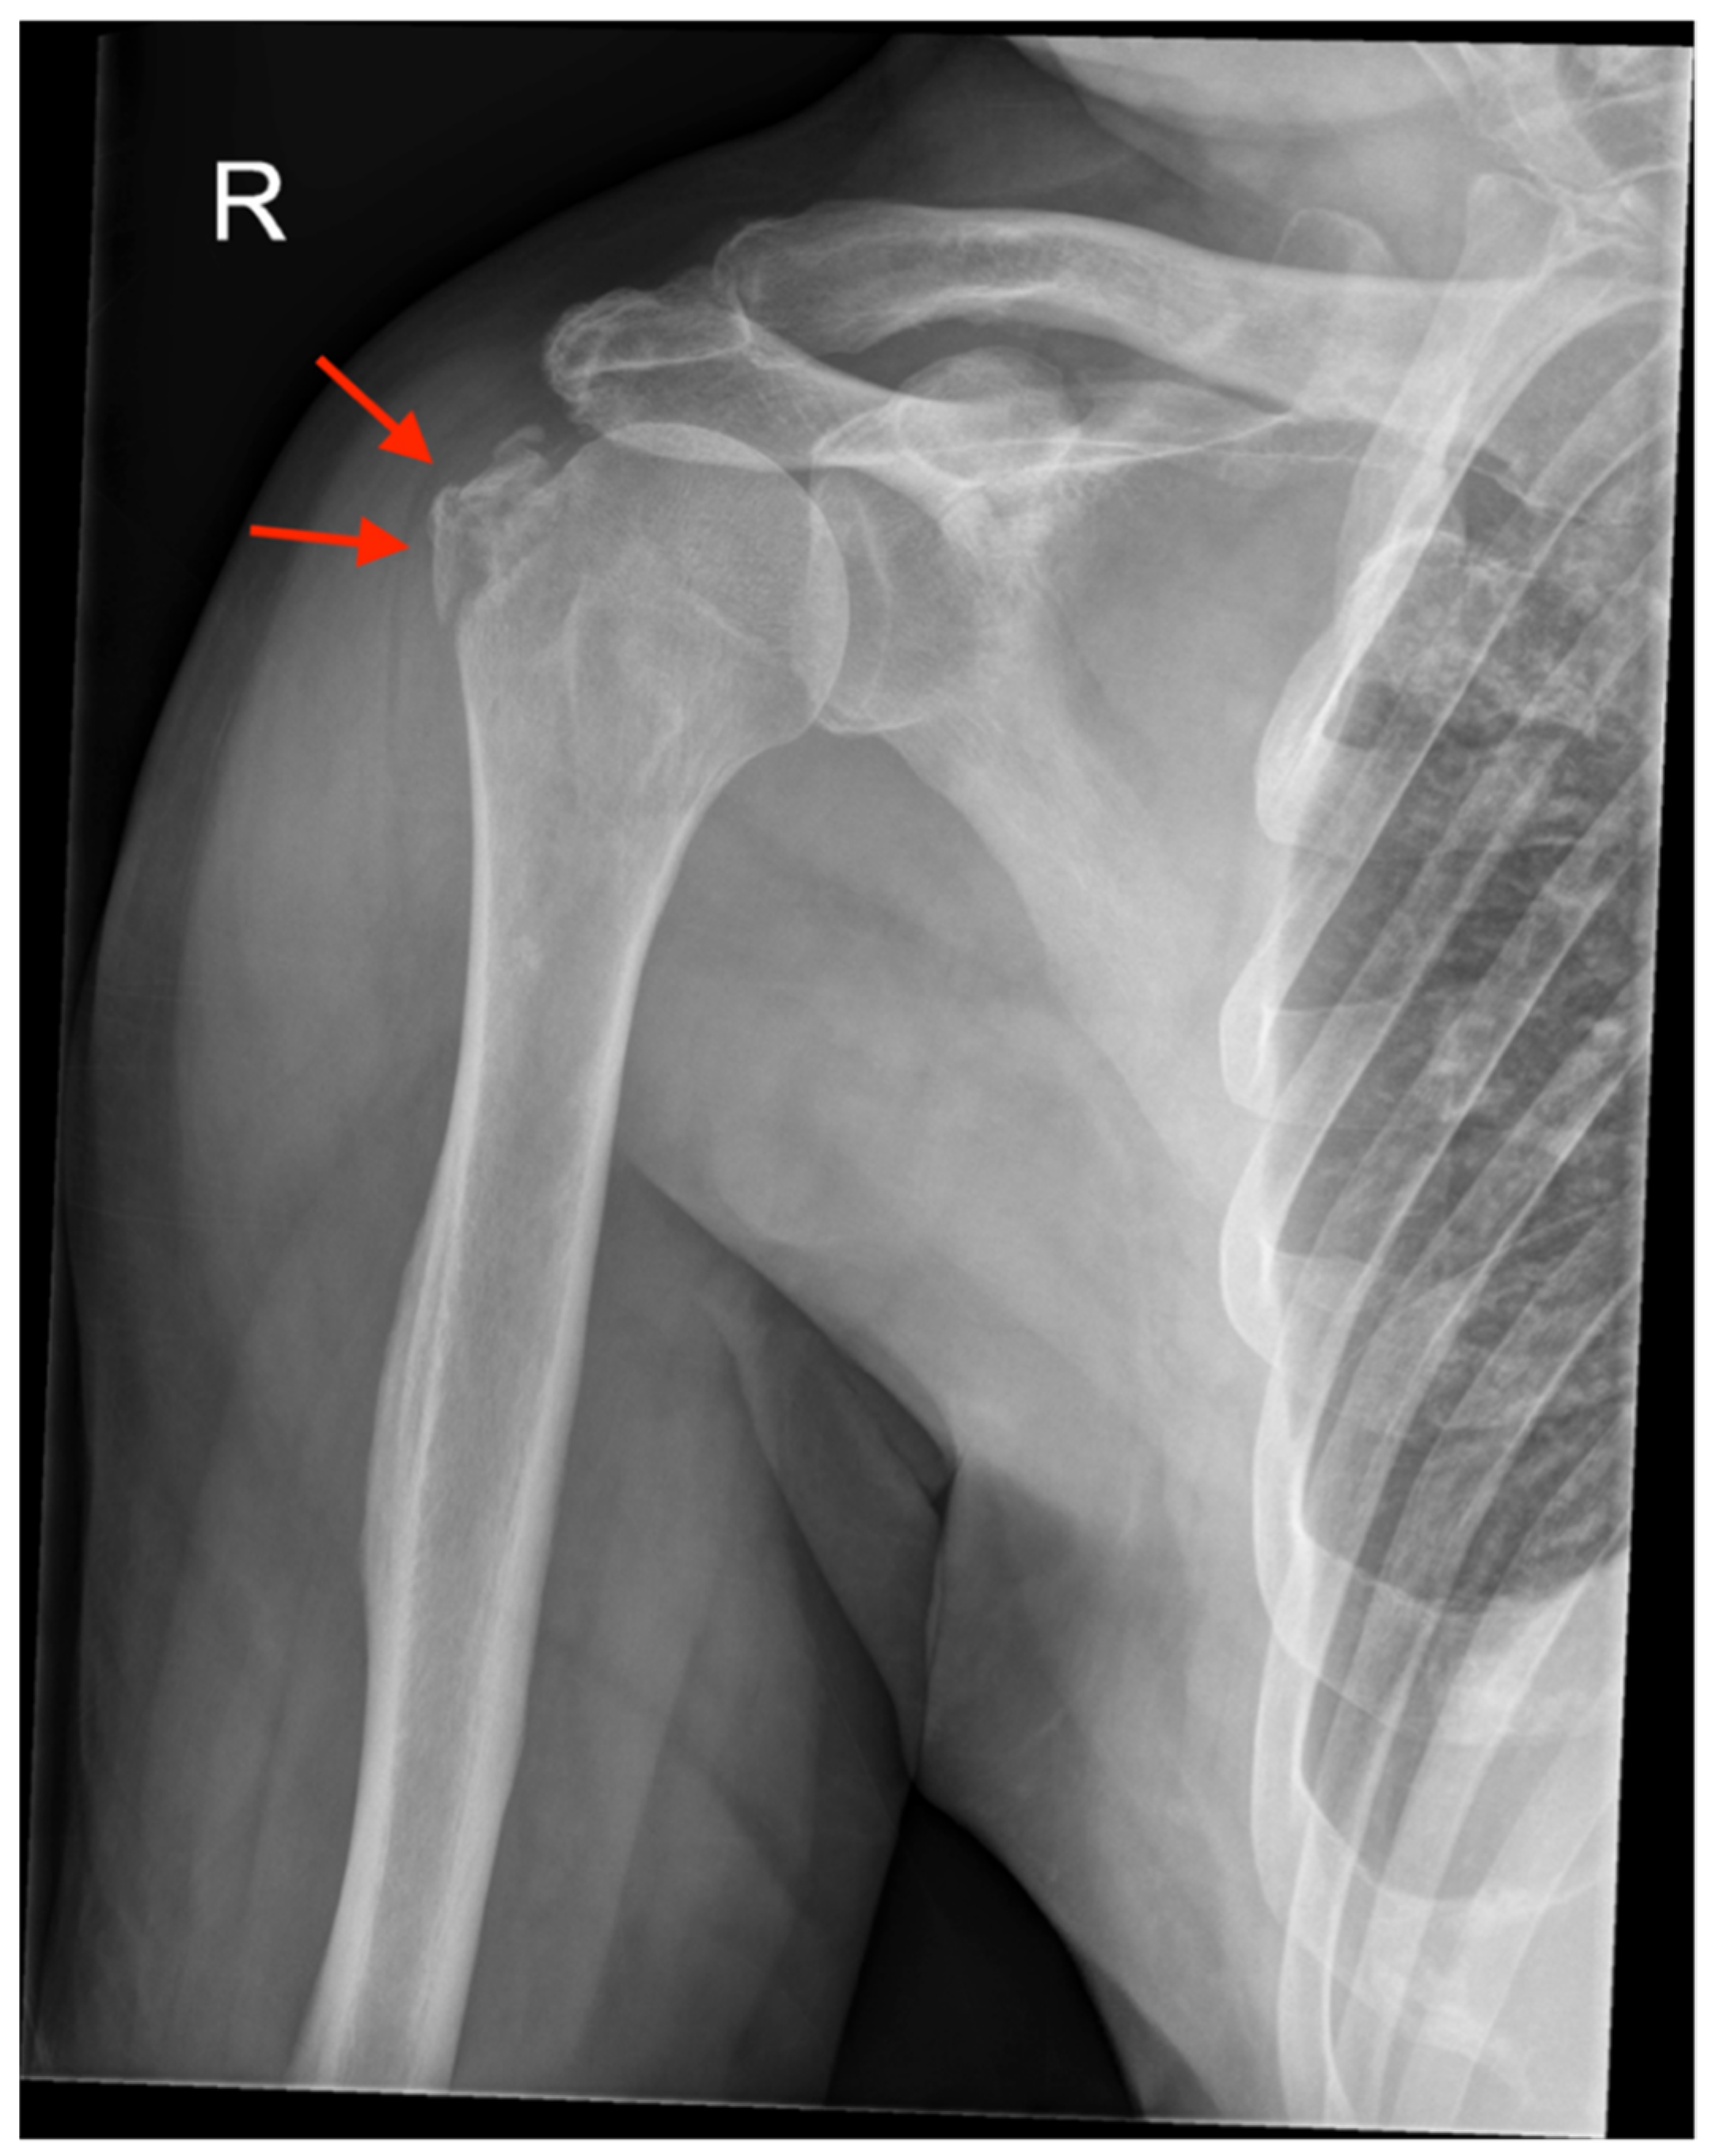

| 2 | - Bony Bankart lesion - Greater tuberosity fracture - Hill-Sachs lesion | None | Bony Bankart lesion | None | Arthroscopic Bankart repair |